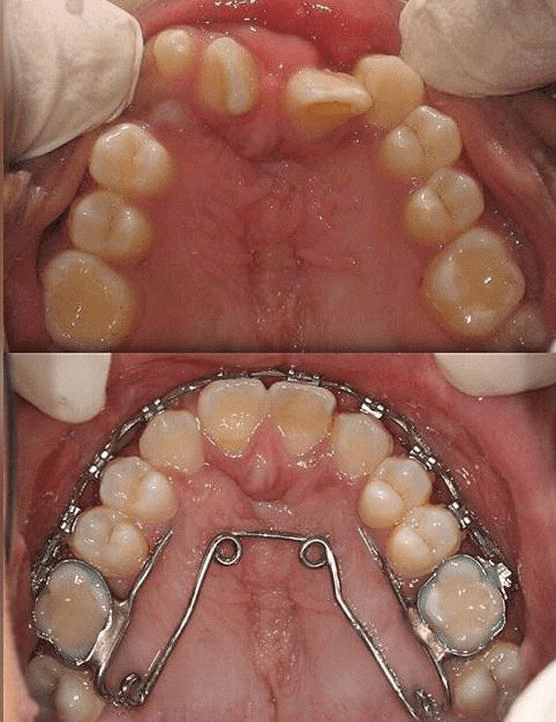

Archwise Distraction Appliance (AWDA) in Cleft Lip and Palate Patient

Left unilateral complete cleft lip and palate case. 4A to 4C before Orthodontics For Cleft Lip And Palate Pdf | cleft lip and palate represent one of the great challenges of craniofacial surgery, with initial descriptions of the condition and surgical repair. Management of children born with cleft lip and palate (clp) has evolved over 100 years. Among the necessary procedures, there are surgeries, orthodontic treatment, laryngologist and speech therapy [ 8, 9 ]. Successful management of the. Orthodontics For Cleft Lip And Palate.

Archwise Distraction Appliance (AWDA) in Cleft Lip and Palate Patient Orthodontics For Cleft Lip And Palate Management of children born with cleft lip and palate (clp) has evolved over 100 years. Among the necessary procedures, there are surgeries, orthodontic treatment, laryngologist and speech therapy [ 8, 9 ]. Successful management of the child born with a cleft lip and palate requires coordinated care provided by a number of. The principal objective of the multidisciplinary dental treatment. Orthodontics For Cleft Lip And Palate.